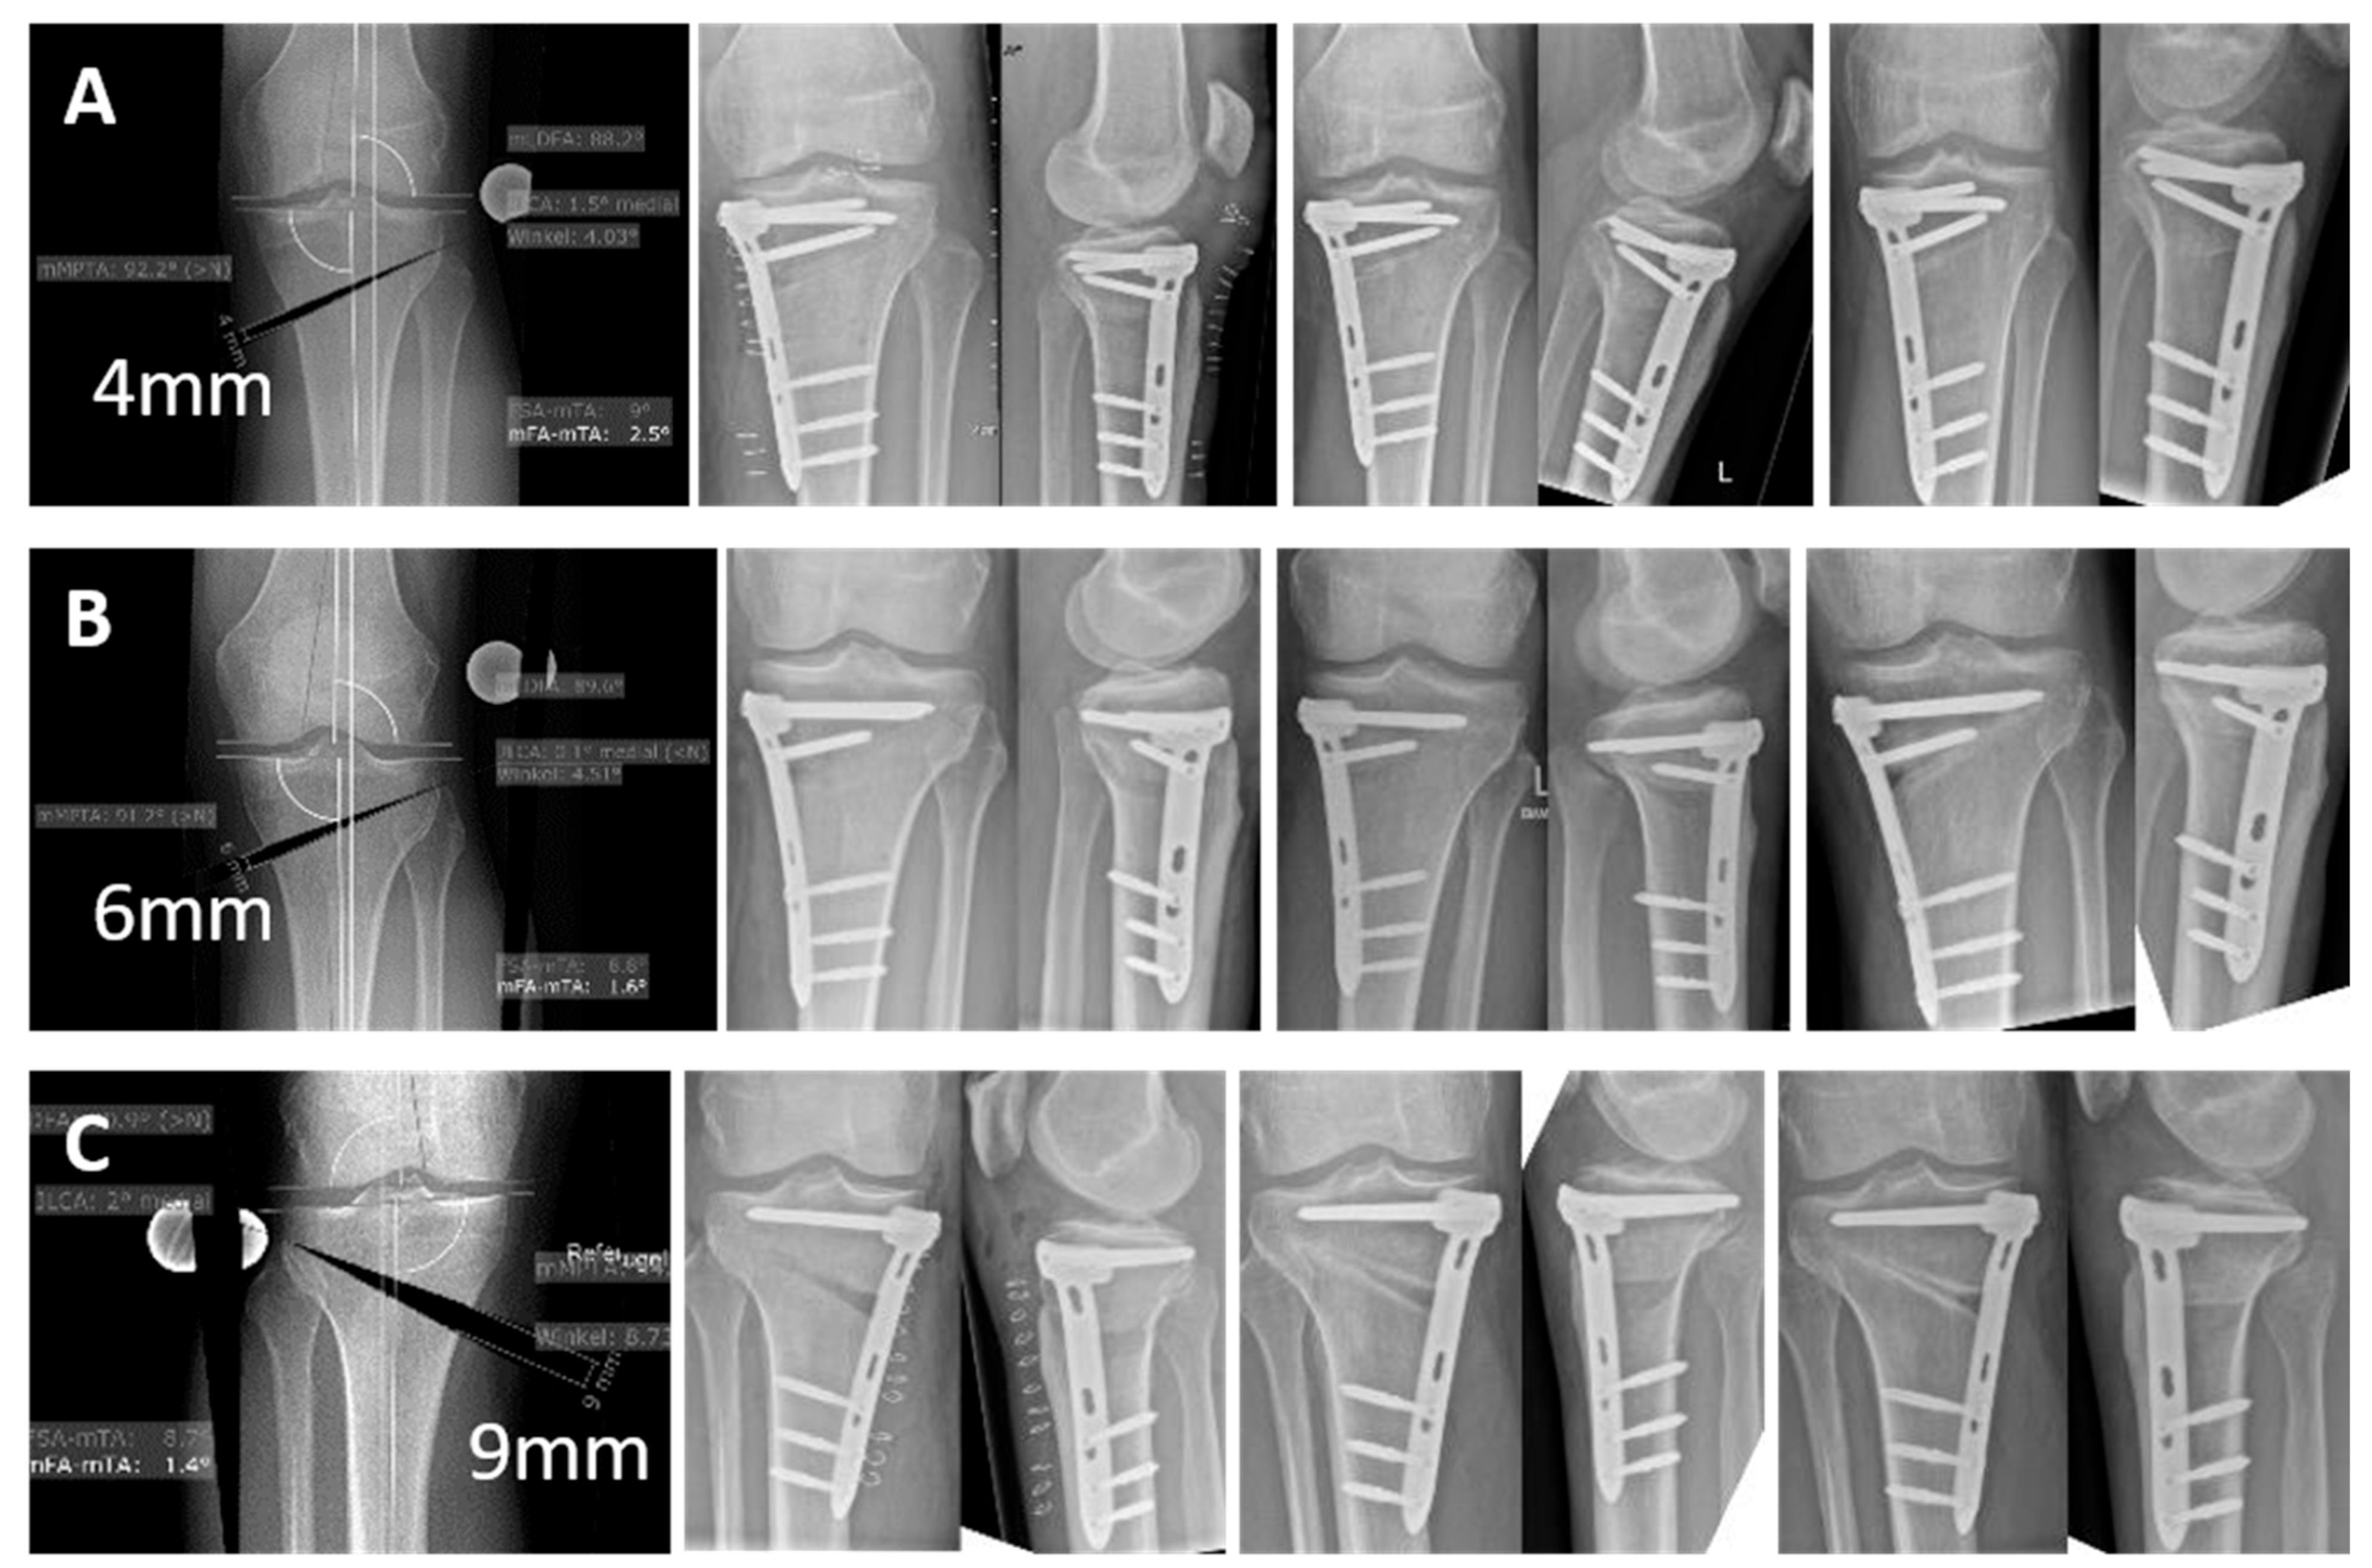

All patients provided full compliance with aftercare. No adverse event, no complication, and no new unknown side effects on patient health have been detected during this study. The removal of implants due to pain or discomfort was not necessary in any patient up to 6 months postoperatively and up to 12 months in five patients and up to 22 months in one patient that had already reached this follow-up. At 6 weeks post-operation, 10% of patients showed radiographic and clinical fracture healing and one patient showed a hinge non-dislocated type 1 [24] fracture (1/10). At 12 weeks, 30% of patients showed complete and 70% adequate radiographic healing while 60% of patients showed a full return to function without length discrepancy, instability, pain, or joint stiffness. At 6 months, 70% of patients showed complete and 30% adequate radiographic healing while 100% of patients showed a full return to function without length discrepancy, instability, pain, or joint stiffness (Figure 2).

Figure 2.

The figure shows 3 exemplary cases of HTOs that were treated with VFLS. The first image in the series shows the pre-operative planning in each case, followed by the X-ray checks post-operatively, after 12 weeks and 6 months. (A) 4 mm opening wedge, (B) 6 mm opening wedge, (C) 9 mm opening wedge.